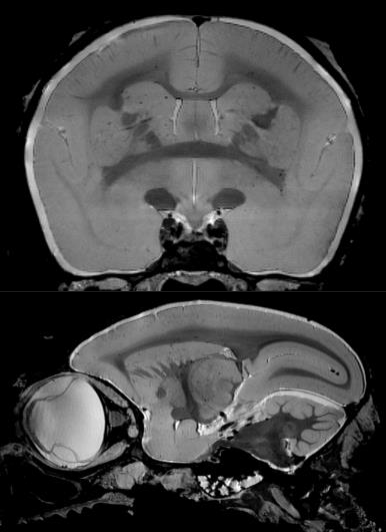

9、猴腦成像

靈長類動物是我國腦科學(xué)計劃中關(guān)鍵實(shí)驗(yàn)動物,對理解大腦的功能運(yùn)轉(zhuǎn)有極大的作用??梢詫?shí)現(xiàn)小型絨猴靈長類動物成像,大大提高空間分辨率。

絨猴的大腦成像: